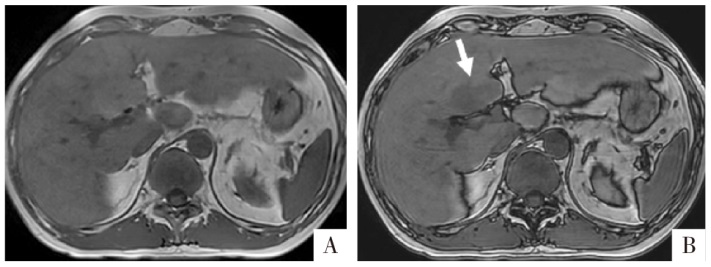

图1

含脂成分的CT与MRI表现。A图,病人女,47岁,肝S5段的血管平滑肌脂肪瘤。CT平扫病灶内可见低密度区域,CT值约为-79 HU,容易确认为脂肪组织。B-D图,病人男,69岁,肝细胞癌脂肪变性。白箭所指为脂肪变性区域,CT平扫上局部呈相对低密度(B),CT值约16 HU,但难以确定为含脂成分;T

1

WI同相位上相应区域呈现稍高信号(C),反相位上相应区域信号明显衰减(D),可以明确判断为脂肪变性。